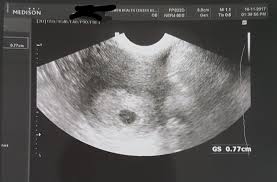

Perkembangan janin saat hamil 11 minggu. Hallo bunda semua,, apa kabar? Ukuran janin 11 minggu sudah sebesar buah ara dengan panjang dari atas sampai ke. Sementara jika anda bertanya janin 5 minggu sebesar apa, maka jawabannya adalah sebesar biji wijen (sesame seed). Saat hamil 11 minggu banyak wanita yang mengalami keputihan. Hati saya sangat risau kerana saya baru hamil 11 minggu. Telinga janin semakin terbentuk malah ia boleh bergerak. Perkembangan janin 10 minggu memang baru sebesar buah plum kering, tapi ia mulai semakin kuat.

Pada saat hamil 5 minggu, janin memiliki bentuk yang jika dilihat lebih mirip seperti kecebong (tadpole). Pada minggu kesebelas usia kehamilan, ukuran janin ibu sudah sebesar bola golf dengan panjang badan dari kepala sampai kaki bisa lebih dari 3 sentimeter. Telinga janin semakin terbentuk malah ia boleh bergerak. Ibu terlalu sibuk dan tidak memperhatikan siklus menstruasinya sering tidak tahu jika dirinya sedang hamil. Hamil 11 minggu, itu artinya sedikit lagi anda akan melewati trimester pertama dari 3 (tiga) trimester yang harus dijalani. Apa hamil minggu ke 2 bisa terdeteksi,bentuk perut sebesar apa? Jika dianalogikan, ukuran janin di dalam kandungan sebesar bola golf. Pengen tau yang dirasakan saat hamil 12 minggu. Yuk, cari tahu perkembangan janin di usia 11 minggu di sini. Telinga mulai terlihat lebih jelas. Seperti apa perkembangan janin 11 minggu kehamilan? Ukuran janin 11 minggu sudah sebesar buah ara dengan panjang dari atas sampai ke. Hal ini masih normal selama cairan yang keluar tidak mengeluarkan bau tidak sedap.

Seperti apa perkembangan janin 11 minggu kehamilan? Saat hamil 11 minggu banyak wanita yang mengalami keputihan. Perkembangan janin saat hamil 11 minggu. Janin pun mungkin akan bergerak saat mendengar ibu bicara. Pada usia kehamilan 11 minggu, berat janin sekitar 7 gram. Pada kehamilan 11 minggu, sejumlah perkembangan yang terjadi pada janin anda adalah sebagai berikut: Hal ini masih normal selama cairan yang keluar tidak mengeluarkan bau tidak sedap. Tapi, anda takkan merasa tendangan bayi lagi.

Ukuran janin 11 minggu sudah sebesar buah ara dengan panjang dari atas sampai ke. Pada minggu kesebelas usia kehamilan, ukuran janin ibu sudah sebesar bola golf dengan panjang badan dari kepala sampai kaki bisa lebih dari 3 sentimeter. Bayi sekarang sebesar jeruk nipis! Ciri utama bayi pada usia kehamilan 11 minggu adalah ukuran janin 11 minggu ini sudah sebesar buah leci. Obat resep dokter zyban, yang terbukti mampu menghentikan kebiasaan merokok, juga tidak dianjurkan saat hamil.

Apa yang sebaiknya dilakukan ibu ketika memasuki masa hamil 21 minggu. Berikut beberapa kondisi yang mengambarkan janin usia 5 minggu seperti apa dalam penjelasan di bawah ini. Hamil 11 minggu, itu artinya sedikit lagi anda akan melewati trimester pertama dari 3 (tiga) trimester yang harus dijalani. Kehamilan pertama pada 2008, saya keguguran ketika berusia 13 minggu. Ini adalah kehamilan ketiga setelah berkahwin 5 tahun dan kami belum mempunyai anak lagi. Hal pertama yang wajib dilakukan oleh ibu hamil usia 21 minggu. Janin anda 11 minggu sekitar 1,6 inci dan beratnya sekitar 0,25 ons. Berat janin berusia 13 minggu umumnya baru mencapai 23 gram dengan panjang antara 6,5 cm hingga 6,8 cm. Tangan dan kakinya juga semakin boleh bergerak. Telinga mulai terlihat lebih jelas. Perkembangan janin ketika hamil 9 ; Pada periode ini, janin dalam kandungan terus mengalami perkembangan. Untuk terhindar dari beberapa masalah yang sering mucul pada usia kehamilan minggu ke 21 seperti nyeri punggung dan kaki bengkak, ada beberapa hal yang sangat dianjurkan untuk dilakukan pada usia kehamilan ini: